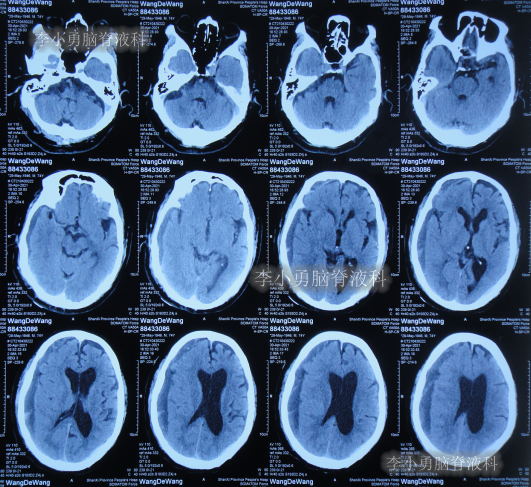

2020年10月29日(发病已8年),因症状一直没有得到改善且呈进行性加重趋势,查头部核磁示脑积水(图-1)。

图-1:2020年10月29日头部核磁